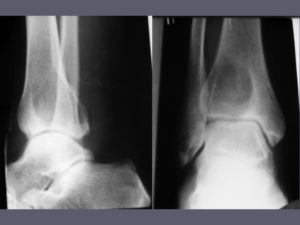

Рентгенография — наиболее распространенный и доступный метод визуализации сарком костей, в специализированных онкологических клиниках точность установления диагноза и стадии процесса превышает 80%. Компьютерная томография позволяет более точно оценить степень повреждения кости и окружающих тканей.

На рентгенограммах выявляется в виде овального или округлого дефекта с четкими контурами, окруженного зоной склерозированной ткани. Лечение – резекция вместе с очагом склероза. Прогноз благоприятный.

На рентгенограммах бедра, голени и других пораженных костей на начальных стадиях выявляется очаг остеопороза со смазанными контурами. В последующем образуется дефект костной ткани, определяется веретенообразное вздутие надкостницы и игольчатый периостит.